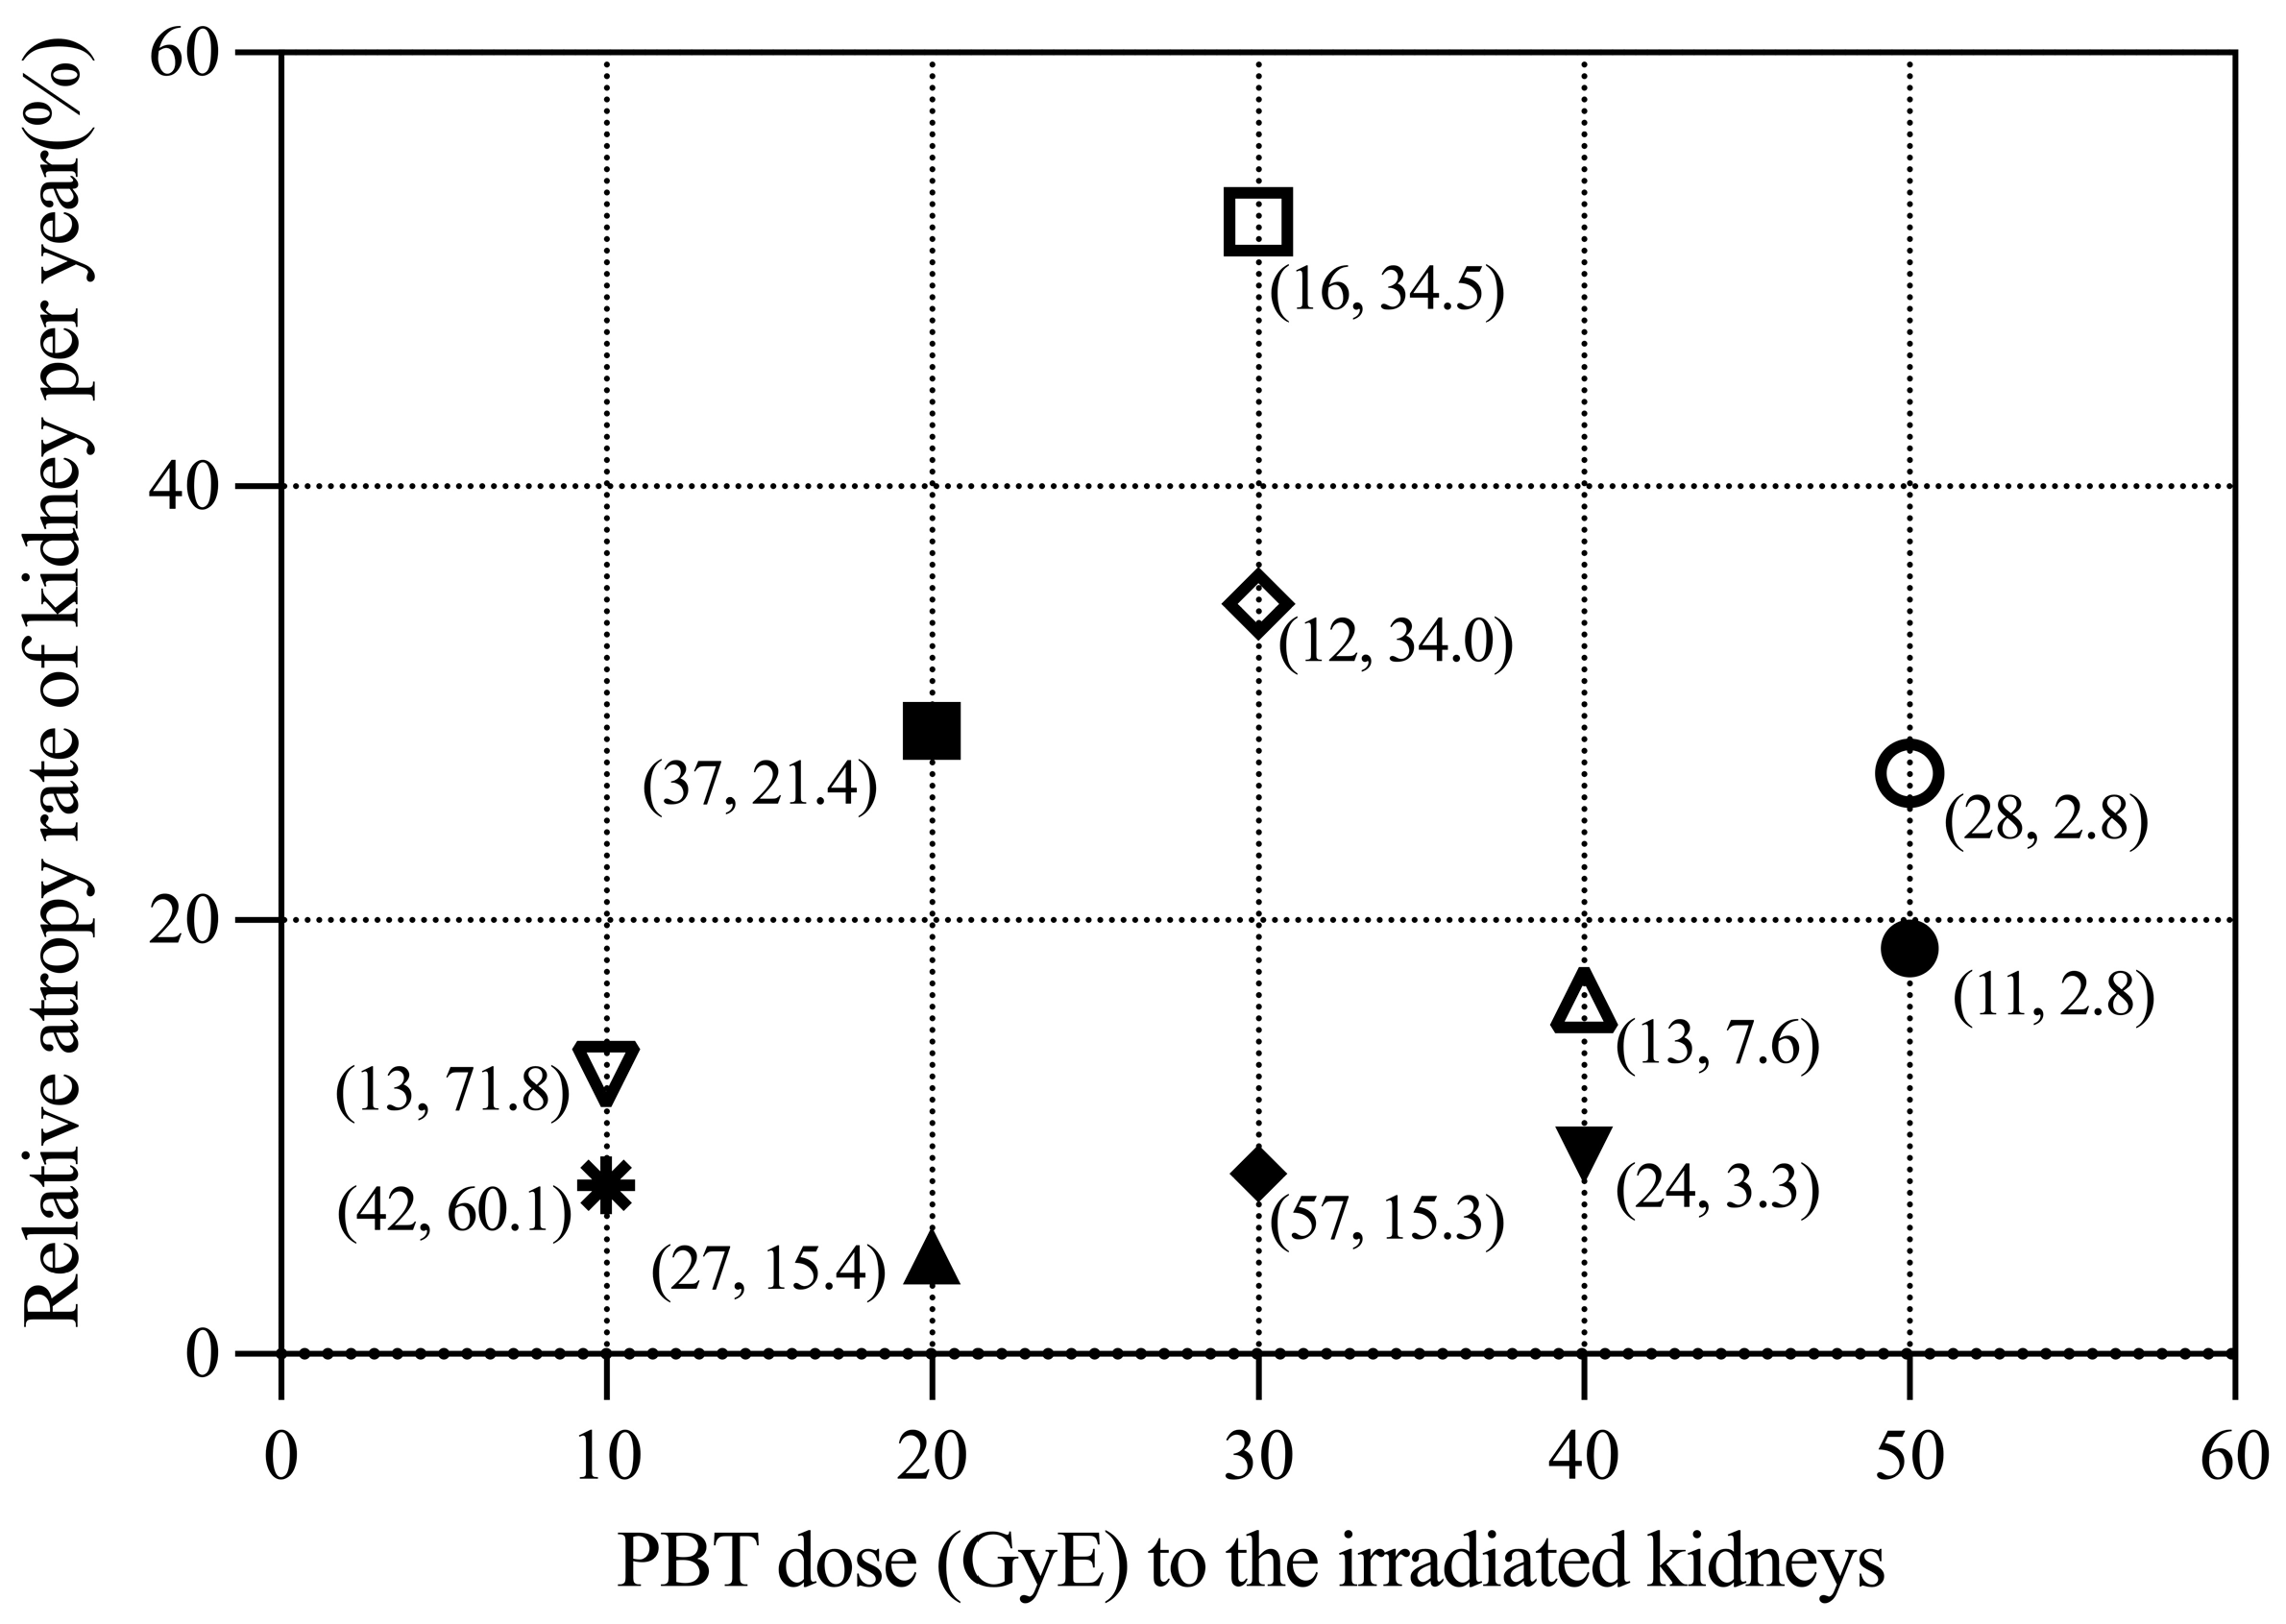

3.2. Renal Volume Changes and DVH Analysis